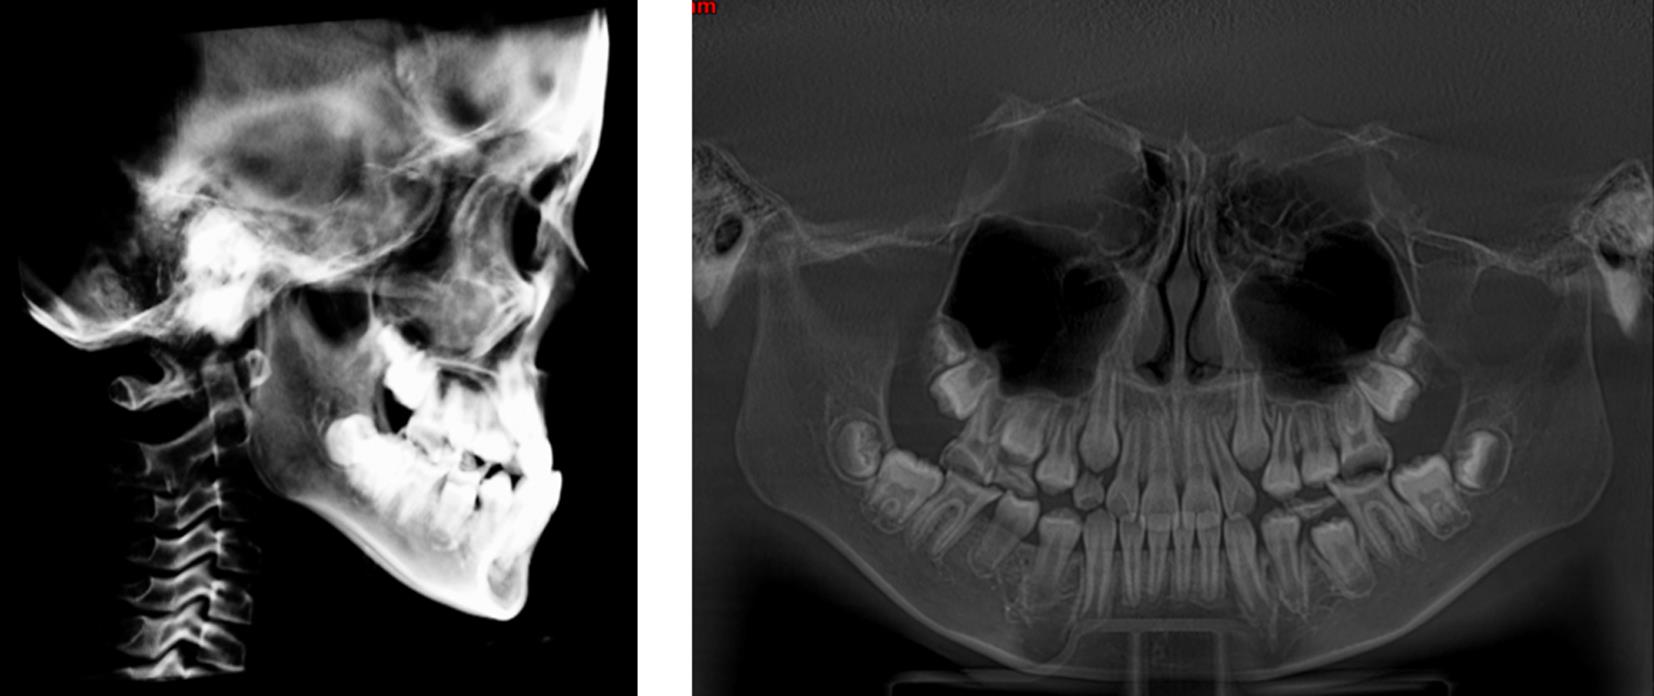

目的 探讨上颌前牵引联合个性化钛板治疗生长发育期骨性Ⅲ类错的临床效果。 方法 纳入2021年5月至2023年5月本院收治的96例生长发育期骨性Ⅲ类错

患者,采用随机数字表法分组,奇数为对照组(n = 48),偶数为观察组(n = 48),对照组予以上颌前牵引治疗,观察组予以上颌前牵引联合个性化钛板治疗,比较两组临床疗效、颌面部软组织指标(LL-EP、NLA、G-SnPg)、硬组织指标[上牙槽座角(SNA)、下牙槽座角(SNB)、上下牙槽座角(ANB)、下颌平面角度(MP-SN)、颌平面与眶耳平面(FH)角度(MP-FH)、上颌骨位置(A-OLP)、下颌骨位置(Pg-OLP)、Y轴角度(Y轴角)]、舌骨位置、牙性指标[H-X、H-Y、H-MP、H-FH]及不良反应发生情况。 结果 治疗后,观察组治疗总有效率较对照组高(P < 0.05);观察组LL-EP较对照组小(P < 0.05);观察组SNA、ANB、MP-SN、MP-FH、A-OLP及Y轴角均较对照组大(P < 0.05);观察组H-X、H-Y较对照组大(P < 0.05);观察组U1-NA较对照组大,覆

较对照组短(P < 0.05);两组不良反应发生情况无显著差异(P > 0.05)。 结论 上颌前牵引联合个性化钛板治疗可显著提升骨性Ⅲ类错

患者的临床疗效,改善软硬组织结构、舌骨位置及牙性指标,且安全性良好。